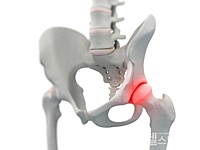

고관절은 골반을 지탱하는 중요한 관절로, 근육과 힘줄로 구성되어 있습니다. 학계에서는 이를 엉덩이 관절이라고 부르며, 신체의 하중을 지탱하는 중요한 역할을 합니다. 고관절은 우리가 정상적으로 서고 움직일 수 있도록 도와주며, 달리기, 점프, 무거운 물건을 들 때 최대 체중의 2~10배에 달하는 압력을 견딥니다. 따라서 적절한 관리가 필요합니다. 오늘은 고관절에서 나타날 수 있는 고관절 통증 증상 10가지에 대해 알아보겠습니다.

고관절 통증의 주요 원인은 퇴행성 질환으로, 나이가 들면서 관절 손상이 발생하는 것입니다. 고관절 자체의 구조적 문제, 주변 근육과 인대의 문제, 척추와 골반 문제 등 다양한 원인이 있습니다. 퇴행성 고관절염, 대퇴골두 무혈성 괴사, 대퇴골 경부 골절, 퇴행성 관절염, 급성 활액막염 등이 주요 원인입니다. 이러한 질환들은 심각한 합병증을 유발할 수 있어 빠른 치료가 필요합니다.